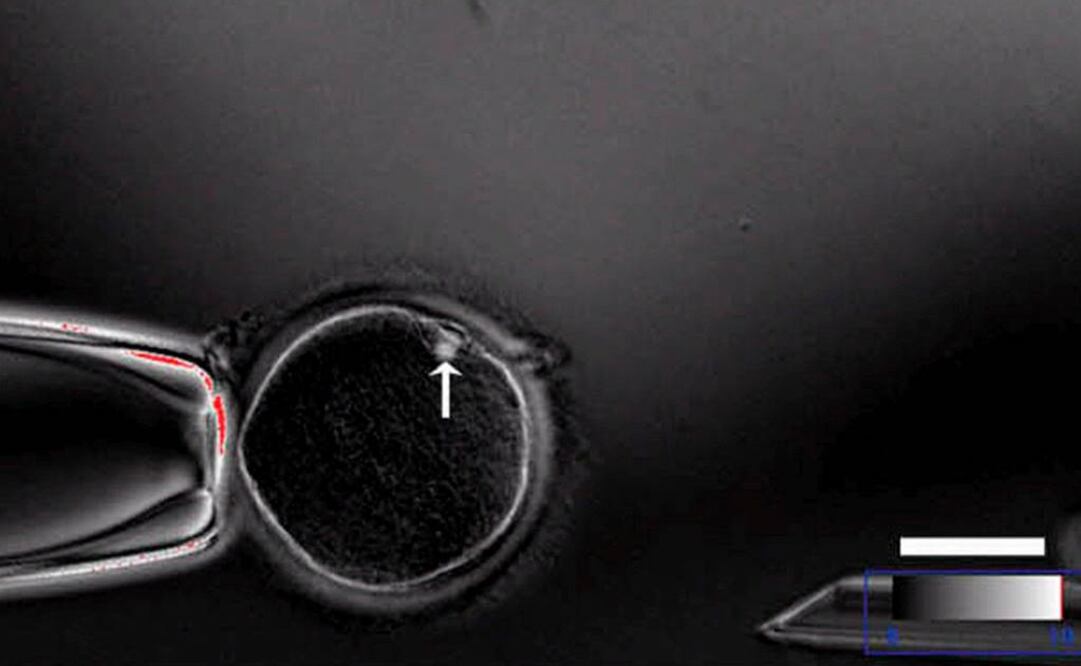

Científicos británicos solicitaron permisos para manipular genes de embriones humanos, en una serie de experimentos destinados a descubrir más sobre las etapas iniciales del desarrollo de las personas.

Meses después de que científicos chinos causaran una conmoción internacional al sostener que tenían embriones humanos modificados genéticamente, una investigadora del Francis Crick Institute en Londres solicitó al regulador sobre temas de fertilidad del Gobierno británico una licencia para desarrollar experimentos similares.

Kathy Niakan, científica especializada en células madre, destacó que no pretende alterar genéticamente a los embriones para usarlos en reproducción humana, sino que busca profundizar el entendimiento científico sobre cómo se desarrollan los embriones humanos saludables.

Científicos de todo el mundo debaten el posible uso futuro de nueva tecnología genética conocida como CRISPR-Cas9, que permite a los investigadores modificar prácticamente cualquier gen que se propongan, incluyendo aquellos contenidos en embriones humanos.